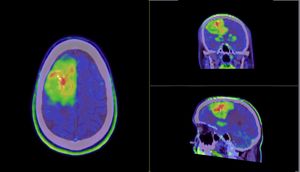

Meet my tumor

Time to cut to the chase. This is my brain tumor. There are many like it, but this one is mine. I've nicknamed him Gary Glia. Gary because it is a seemingly unpopular name nowadays in the UK (can't imagine why...), so it seemed quite appropriate. And Glia because it is the type of cell in my brain that has gone tumorous.

Gary is an unpaying tenant that has taken up residence in my head. What a prick!

A few days later I had a meeting with the neurosurgeon where I was shown the above images. Now full respect to the neurosurgeon I spoke too, I like him. He was straight down the line and straight to the point. No sugar coating, no forewarning about the size of the tumor. After 30 minutes of chatting about all of the above, he simply pulled his phone out and showed me image number 1 you see above. You could say I wasn't exactly prepared for the image, a understatement if ever there was one. But in all honesty I don't think I ever would be. So it was a good tactic. Make it quick and painless, just like ripping off a band-aid!

So, what do we know about Gary?

- He's big... look at the size of this unit. I'm amazed I can even function at all to be honest!

- He's of the type called oligodendroglioma and currently believed to be a Grade 2 (slow growing) tumor. Wondering how you pronounce that? Isn't YouTube great!

- He's very rare, with only 1,217 people diagnosed with this type in the US every year out of a population of 328 million!

- He's a number of years old. The neurosurgeon said a couple of years, but I personally suspect he could be 7 or 8 years old due to other symptoms in my past I now think could be related.

- He's a prick.